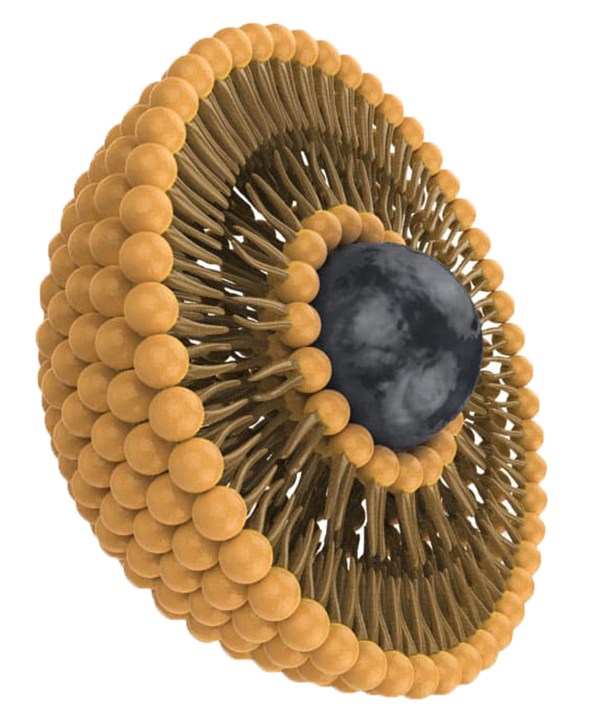

PUREDOSE® Micelle Liposomal

Magnesium

This highly absorbable magnesium is formulated with a state-of-the-art micelle liposomal coating.

And this is a breakthrough magnesium absorption technology that no generic type of magnesium we tried and tested contains.

Remember how I said that most magnesium supplements rarely get absorbed by the body and are damaged by our gut acid before we can even benefit from it?

That's precisely why many magnesium supplements you find in stores only have around a 4% absorption rate… Which is simply not enough to truly work…

However, when magnesium bisglycinate is coated with this state-of-the-art micelle liposomal protective layer, it can boost the absorption rate by up to 800%!

This is about 8 times the absorption rate of the typical tablet and powder form of magnesium bisglycinate available on the market.

YES – 8 times!

And beyond protection against harsh stomach acids and boosting absorption rate, the micelle liposomal coating also helps the body deliver the mineral into our bones where it needs to be stored.

As I mentioned, even if magnesium is absorbed, it needs help with deliverability, and if it sits in the blood for too long, it'll just get flushed out within 24 hours.

And worst, high magnesium in our blood can lead to joint deterioration, kidney failure, kidney stones, muscle weakness, and even cause deficiency in other minerals such as calcium.

However, thanks to this unique micelle liposomal breakthrough, it takes care of this problem immediately.

In fact, this unique coating is so effective that the magnesium starts to get absorbed the moment it enters your mouth and touches your throat!